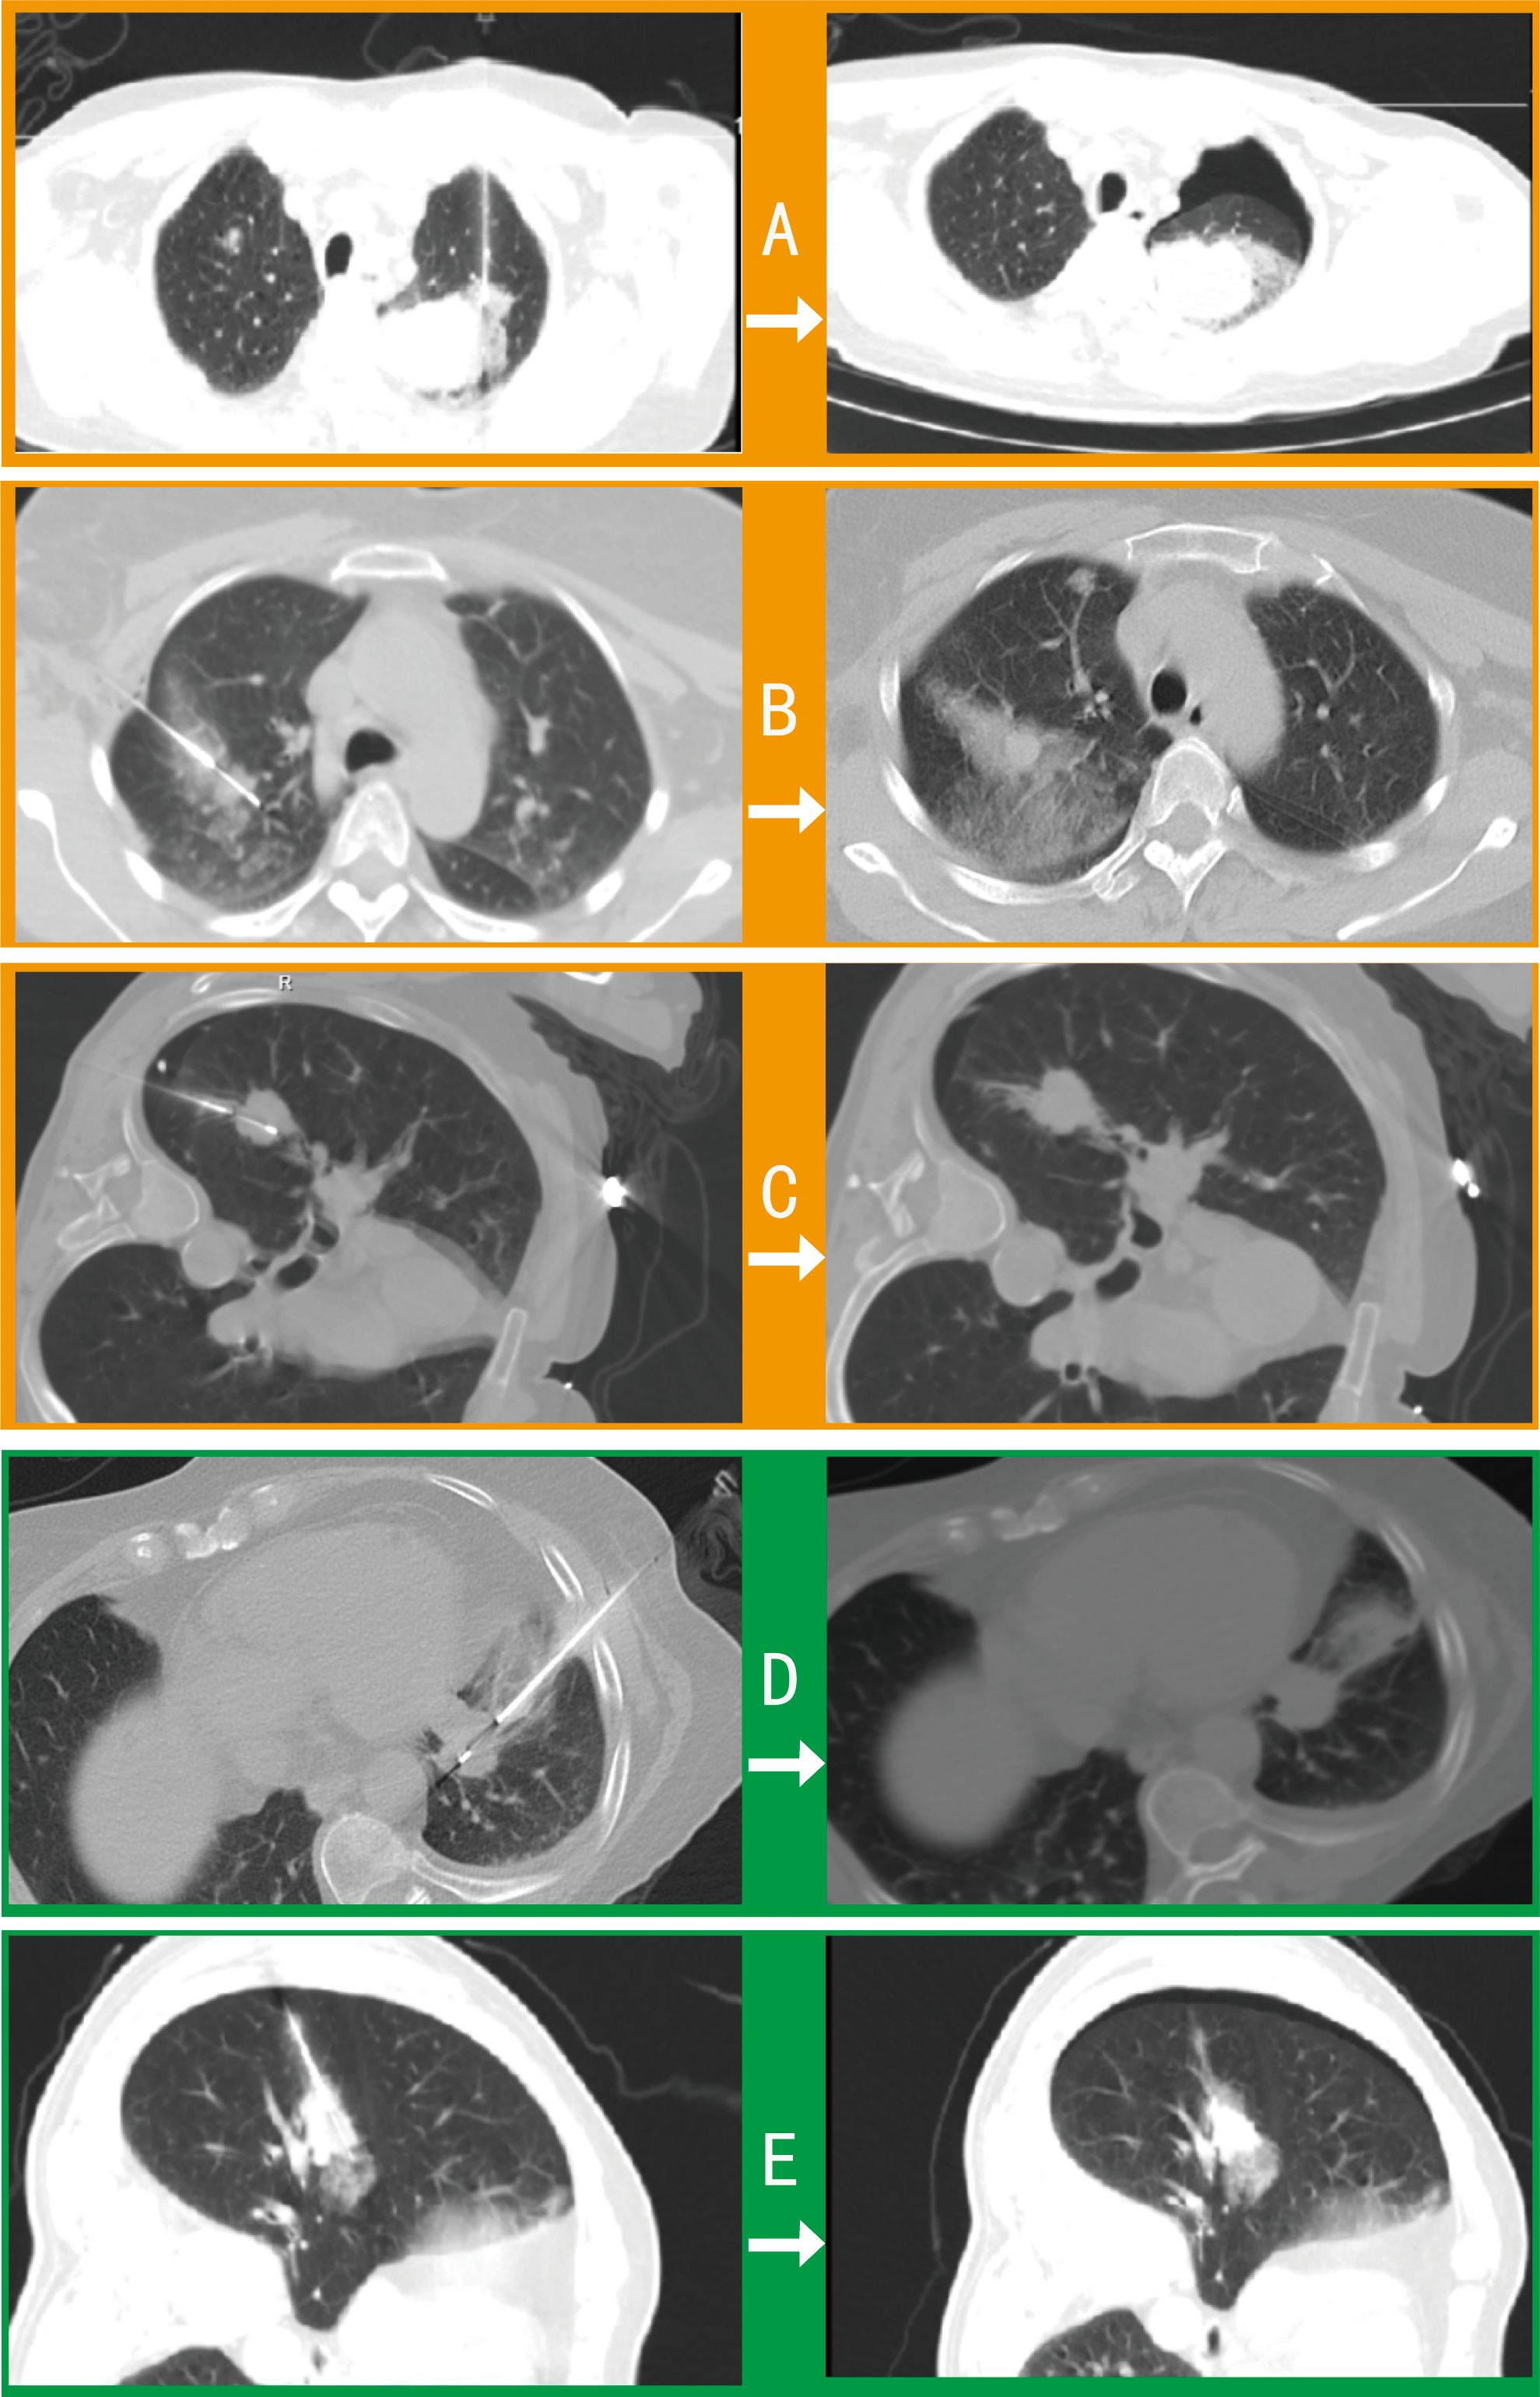

Among 42 pulmonary biopsy cases, 33 (78.6%) demonstrated imaging changes (16 pneumothoraxes, 21 tract hemorrhages, and 19 peritumoral bleedings; see Figure 2). After gelatin sponge-thrombin sealing, only 1 (3.0%) radiologic pneumothorax progressed to symptomatic status requiring drainage, while 32 (97.0%) remained clinically insignificant. Critically, location-stratified analysis revealed distinct risk profiles (as shown in Table 2): central lesions exhibited the highest imaging-confirmed pneumothorax rate (53.8%, 7/13), yet only 7.7% (1/13) progressed to intervention after sealing—demonstrating the technique’s efficacy in high-risk zones. Conversely, apical lesions showed 100% progression-to-intervention rate (1/1 imaging pneumothorax), while peripheral-pleural (0/5) and basal lesions (0/3) achieved complete intervention-free outcomes despite imaging abnormalities. Compared with conventional pulmonary biopsies (meta-analysis: 25.3% radiologic pneumothorax rate with 22.1% intervention rate) (18), this sealing technique achieved an 86.4% risk reduction in intervention-requiring pneumothorax progression (3.0% vs 22.1%, p < 0.001), with an overall intervention rate of merely 2.4% (1/42) versus 5.6% in traditional methods.

Figure 2

Axial CT scans (A-E) comparing intraprocedural (left) and postprocedural (right) lung images. Cases show complications including pneumothorax and hemorrhage, with varying clinical outcomes from drainage to no intervention.

Figure 2. Comparative imaging of post-biopsy complications in pulmonary procedures. Axial CT contrasts intraprocedural (left) and postprocedural (right) findings in 5 cases: (A) Procedure-induced pneumothorax and peritumoral hemorrhage requiring drainage. (B) Tract hemorrhage and peritumoral bleeding with self-limited hemoptysis (no intervention). (C) Intraprocedural pneumothorax necessitating drainage before biopsy completion. (D) Asymptomatic tract hemorrhage. (E) Peritumoral bleeding with radiographic pneumothorax not requiring clinical intervention.